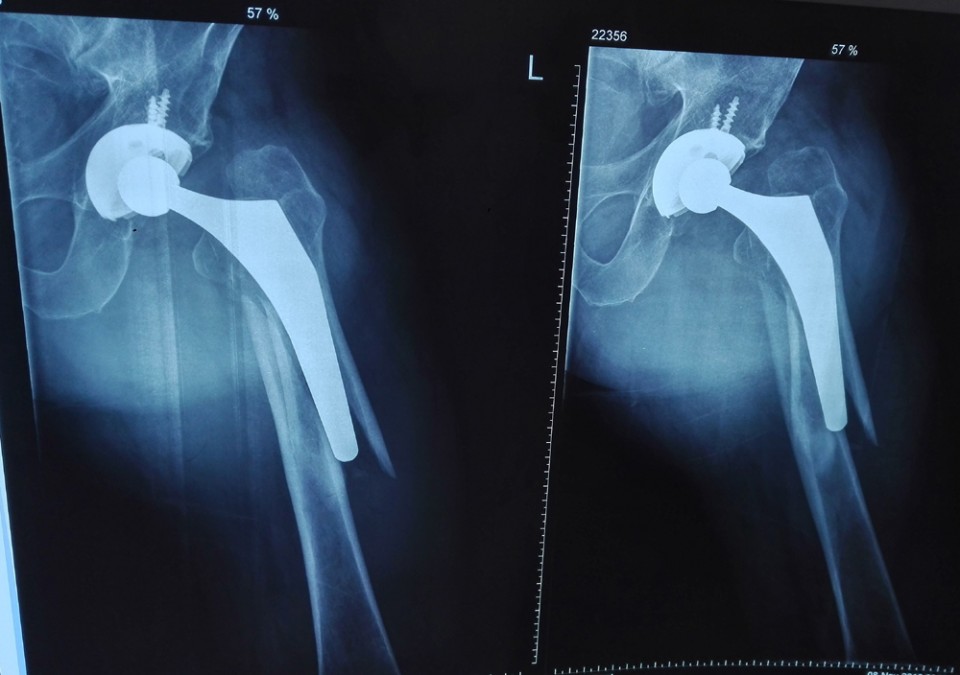

图1.翻修术前

近日,我院成功为一名65岁的男性患者实施了假体周围骨折翻修手术。患者3年前在其他医院曾经做过全髋置换术,一周又前因为摔伤而导致假体周围骨折。据主刀医生胡勇主任介绍,该例假体周围骨折根据Vancouver分型为B2型,假体失去稳定性,需行髋关节假体翻修术。手术十分顺利,术后恢复满意,患者顺利出院。